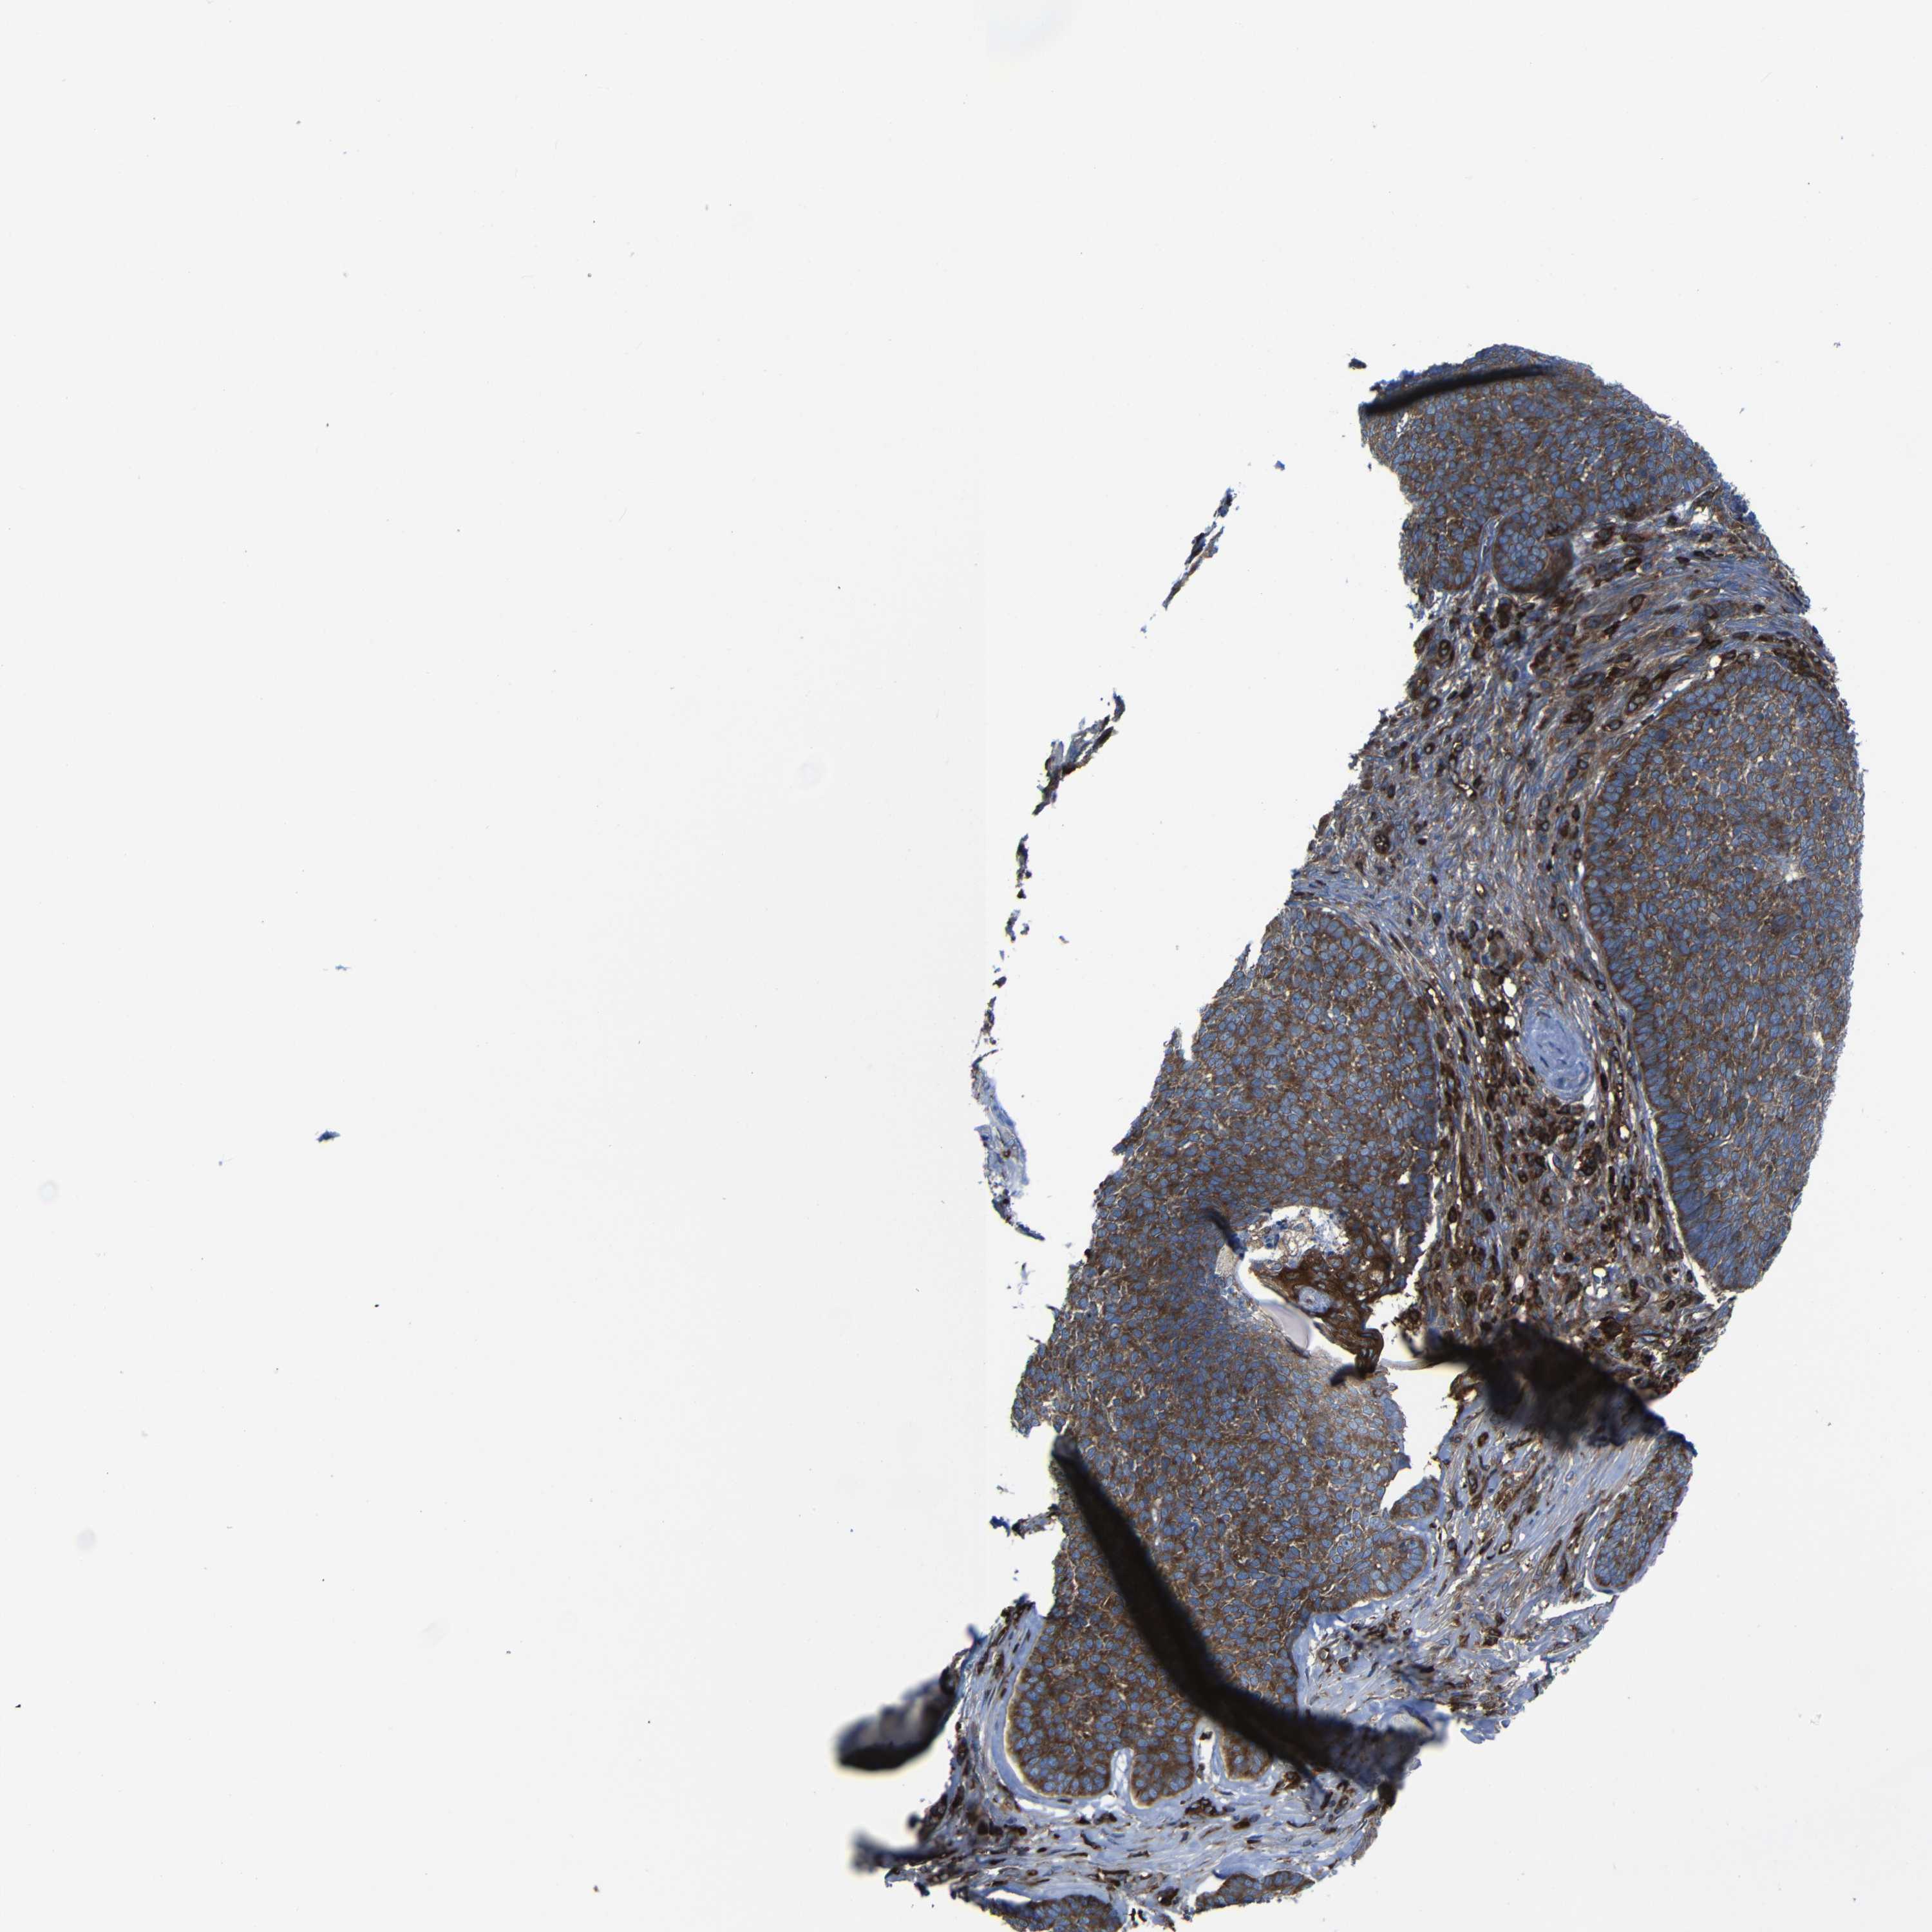

SKIN CANCER - Protein expressioni

A mouse-over function shows sample information and annotation data. Click on an image to view it in a full screen mode. Samples can be filtered based on level of antibody staining by selecting one or several of the following categories: high, medium, low and not detected. The assay and annotation is described here.

Each image is clickable and will lead to virtual microscopy that enables deeper exploration of all samples and also displays staining intensity scores, fraction scores and subcellular localization as well as patient and tissue information for each sample.

Antibody HPA012924

Squamous cell carcinoma, NOS